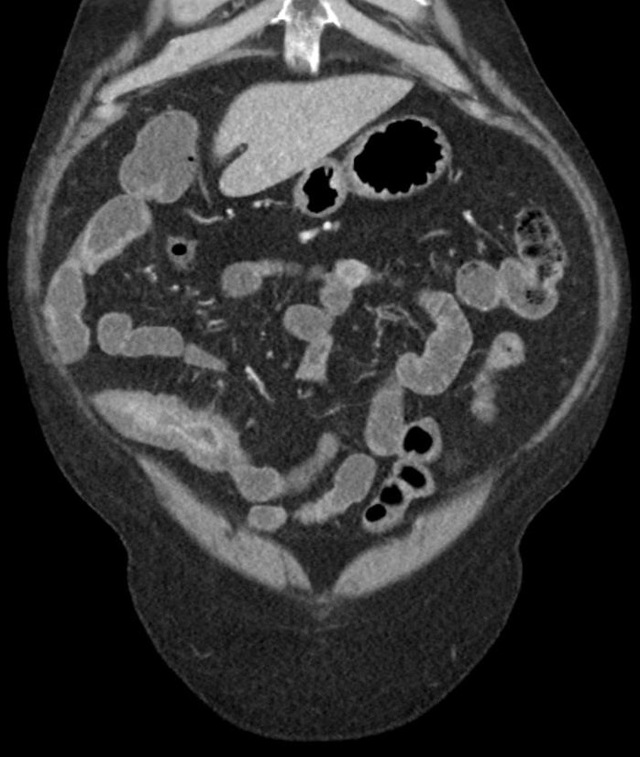

首先,克罗恩病这东西,真的是让人又爱又恨。它会让你肚子疼,拉肚子,还可能让你营养不良。所以,护理诊断上,我们得重点关注这些症状。比如,我每次肚子一疼,就知道是克罗恩病在作怪,这时候就得赶紧调整饮食,少吃那些刺激性的食物,多吃点易消化的。